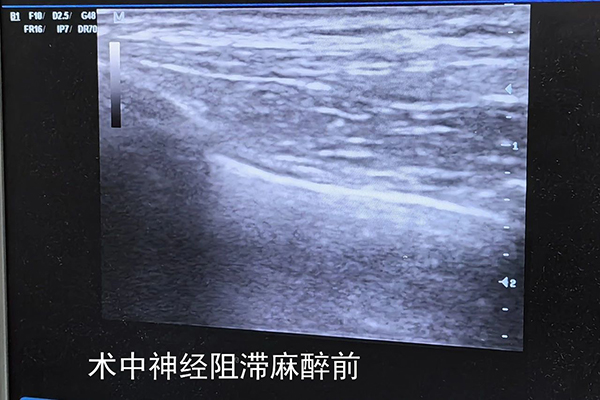

手术由普外科副主任医师李华志和主治医师佟凡携手完成。鉴于患者体型瘦弱,加之左乳肿瘤已逾一年未接受治疗,其直径已增至5厘米。麻醉科主治医师杜鹃在术前为患者量身定制了神经阻滞麻醉方案。得益于手术团队的高超技艺与完美协作,患者顺利完成了根治性手术,并在术后第二天顺利出院。

▲患者术中神经阻滞麻醉前后对比